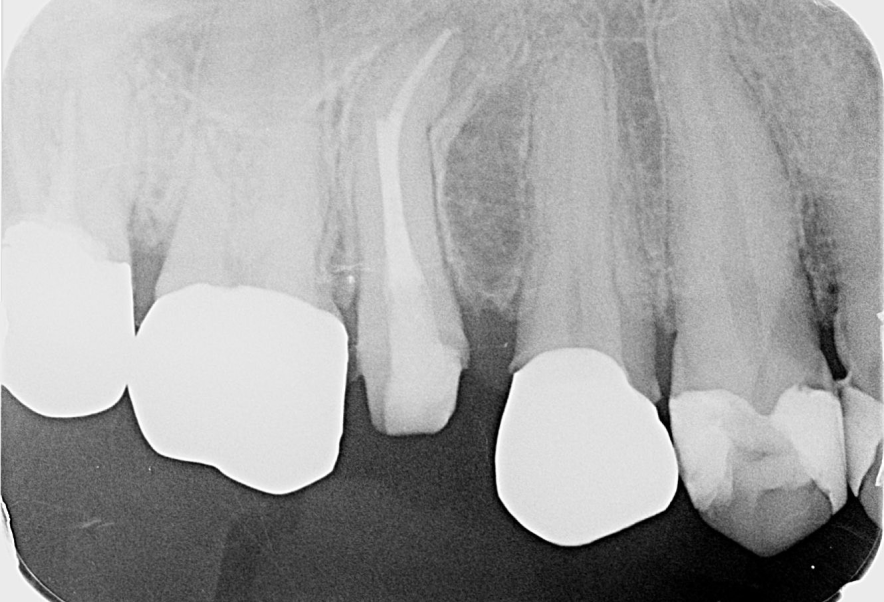

• 歯科用CTでの細かい診査・診断

歯科用CTでの細かい診査・診断

根管の本数や形は人それぞれ違い、とても複雑な形状をしています。CTを使って根管の構造と病巣の広がりを立体画像で正確に把握し治療を進めていきます。